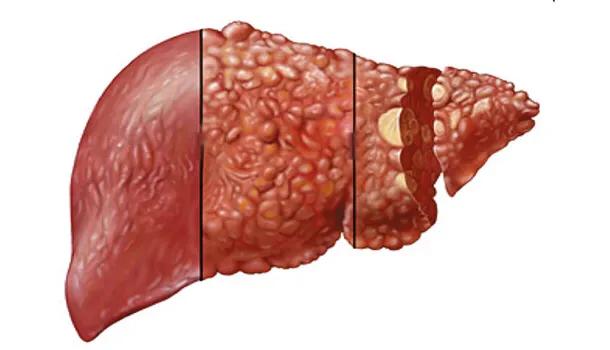

IV. fettleibigkeit

Bei fettleibigen Menschen ist die Wahrscheinlichkeit größer, dass sie eine Fettleber haben, die bei fast 30 % der Erwachsenen in China vorkommt. Wir wissen, dass eine Fettleber zu Krebs werden kann, wenn sie nicht aktiv kontrolliert wird: Fettleber → Steatohepatitis → Leberfibrose → Zirrhose → Leberkrebs. Einige Studien zeigen, dass Patienten mit Leberkrebs, der durch eine Fettleber verursacht wurde, eine kürzere Überlebenszeit haben und seltener eine Lebertransplantation erhalten.

Zweitens, oft essen Lebensmittel, die hohe Menge an tierischem Fett, übermäßige Ernährung mit Fett Lebensmittel, der Körper den Stoffwechsel nicht verbraucht wird, wird es in der Leber und die Bildung von subkutanem Fett, die Leber enthält zu viel Fett wird in Fettleber, Fettleber ~ Zirrhose ~ Leberkrebs, der Prozess als die Inzidenz von einer gesunden Leber ist mehrmals höher.